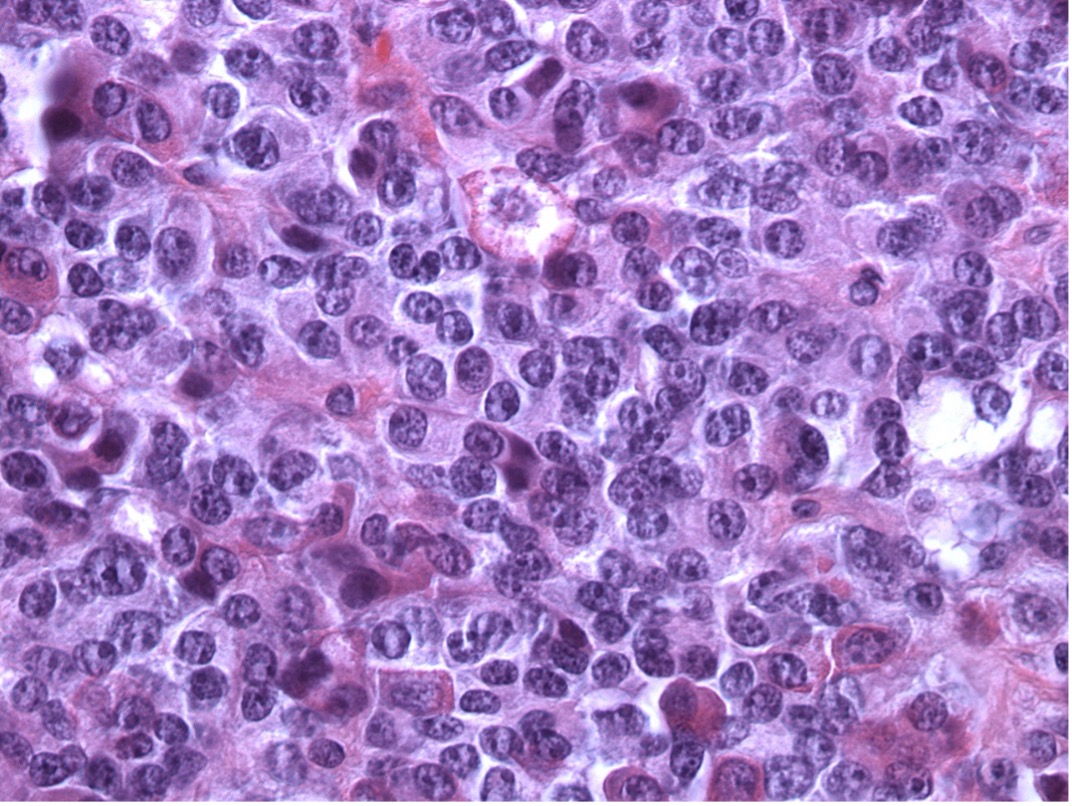

A 31 year-old man presented with enlarged supraorbital ridges, wide nose, and prognathism. Imaging studies demonstrate a thickened skull, enlarged frontal sinus, and a sella mass. Histopathology: solid neoplasm, interrupted by “pseudoglandular” spaces. Cells had eosinophilic cytoplasm and prominent nucleoli:

Discussion: Densely granulated somatotroph adenomas are eosinophilic and have a solid growth pattern. The pseudoglandular areas and prominent nucleoli are often seen in TSH adenomas. Pit-1 drives both GH and TSH (and Prolactin) producing adenomas. This patient had elevated TSH and GH on his lab studies. GH (left) and TSH (right) are below: